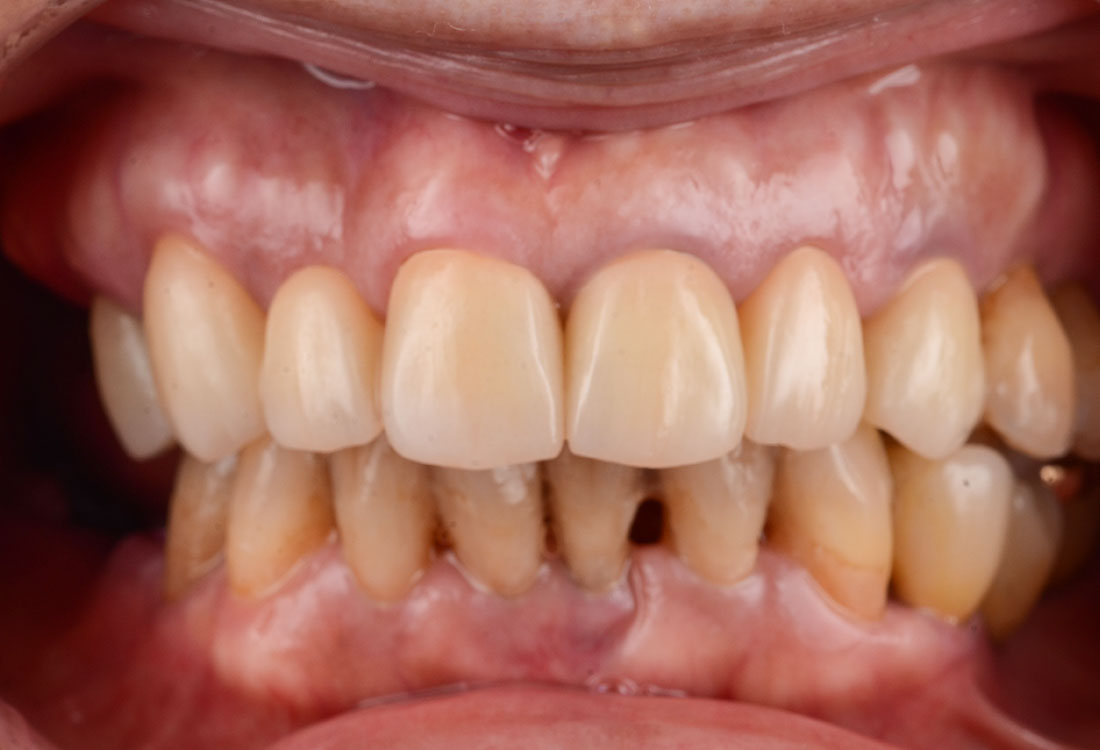

ご相談内容

- 歯の形と見た目が気になる

- 真っ白ではなく色を元の歯の色に合わせてほしい

今回は着色したジルコニアを選択しました。

治療後

着色した被せ物を使うことでとても自然な仕上がりになりました。